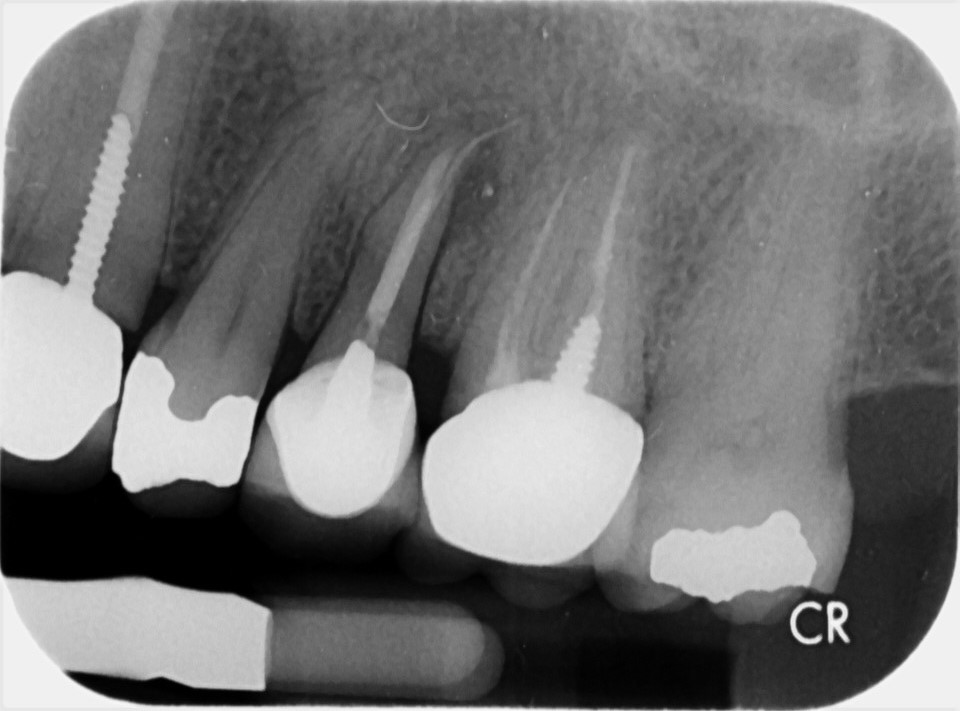

Buccal root of the bifurcated maxillary premolar—a danger zone during Lip Burn During Root Canal Sodium hypochlorite (naocl) is the most common irrigant used in modern endodontics. Nerve injury and an ensuing altered sensation. It is highly effective at dissolving. When it comes to nerve damage after a root canal, there are several. Went in for my root canal today. Why do we use it? What are the symptoms of nerve damage after root canal?. Lip Burn During Root Canal.

Buccal root of the bifurcated maxillary premolar—a danger zone during Lip Burn During Root Canal What are the symptoms of nerve damage after root canal? Sodium hypochlorite (naocl) is the most common irrigant used in modern endodontics. To reduce or eliminate pulpal remnants. When it comes to nerve damage after a root canal, there are several. Went in for my root canal today. It is highly effective at dissolving. I was terrified just like last. Lip Burn During Root Canal.

Buccal root of the bifurcated maxillary premolar—a danger zone during Lip Burn During Root Canal The patient reported an episode of sudden acute pain and severe swelling in the. Sodium hypochlorite (naocl) is the most common irrigant used in modern endodontics. Went in for my root canal today. I was terrified just like last time, even though i knew he would numb me up good. What are the symptoms of nerve damage after root canal?. Lip Burn During Root Canal.